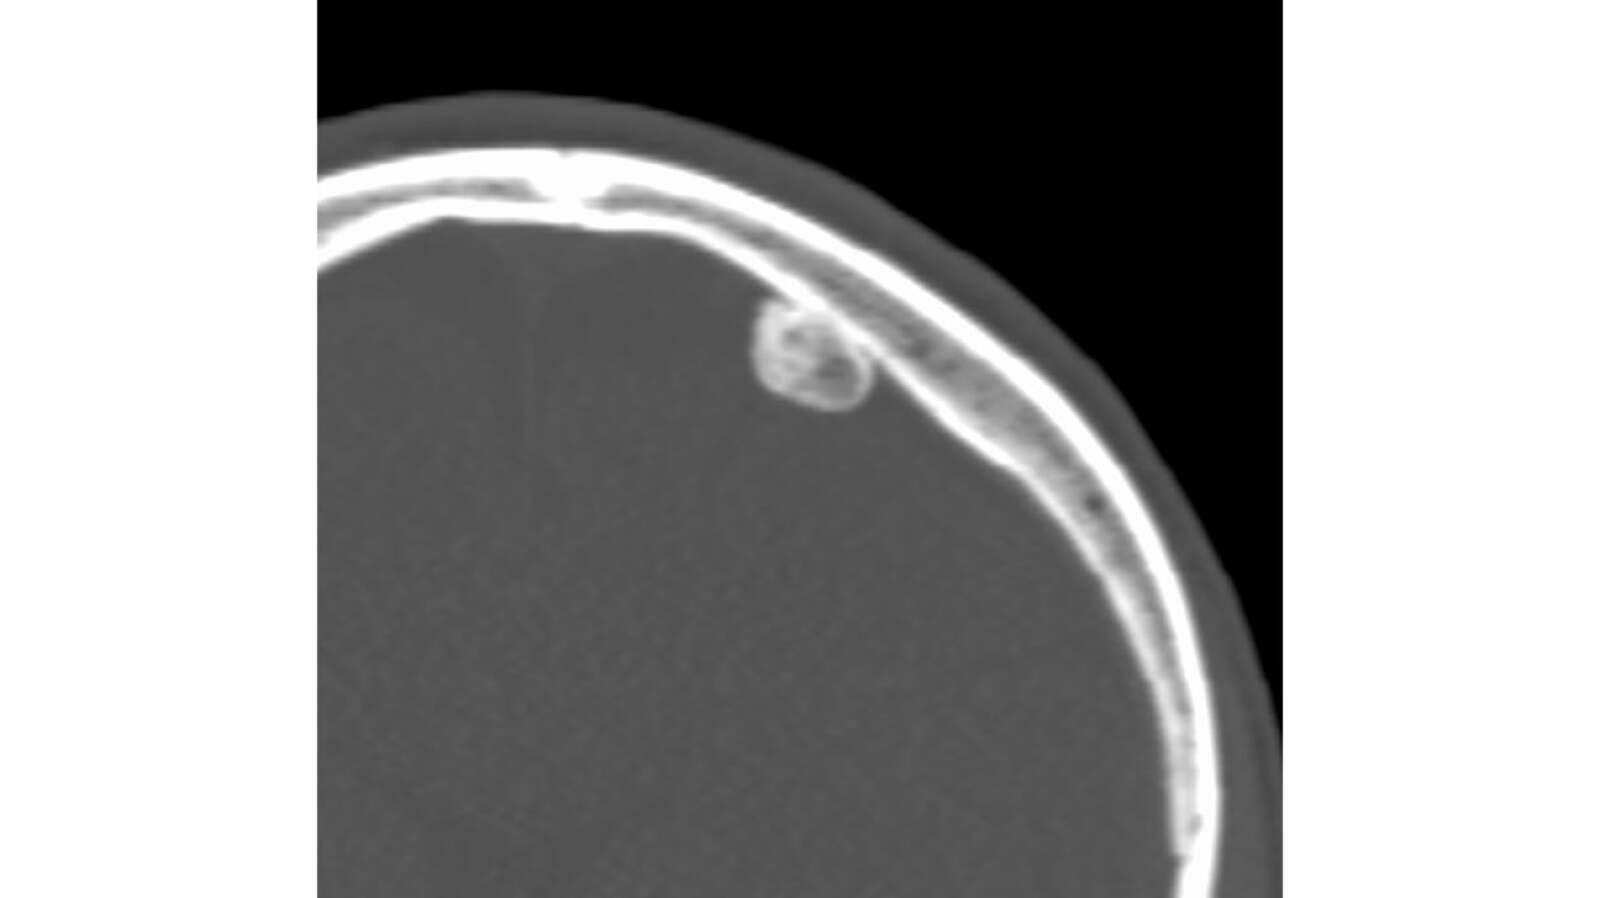

From www.ncbi.nlm.nih.gov

[Figure, Osteoid Osteoma in the pars...] StatPearls NCBI Bookshelf Osteoma Dentistry Definition an osteoma is a benign bone tumor that typically forms on the skull. osteoma is a benign neoplasm characterized by proliferation of either. an osteoma is a benign bone lesion with no clear pathogenesis, almost exclusive to the craniofacial area. Depending on where they develop, osteomas can sometimes cause symptoms such as headaches or sinus. An osteoma. Osteoma Dentistry Definition.

From atlas.mudr.org

Radiology case Osteoma of external auditory meatus Osteoma Dentistry Definition an osteoma is a benign bone tumor that typically forms on the skull. osteoma is a benign neoplasm characterized by proliferation of either. an osteoma is a benign bone lesion with no clear pathogenesis, almost exclusive to the craniofacial area. Depending on where they develop, osteomas can sometimes cause symptoms such as headaches or sinus. an. Osteoma Dentistry Definition.